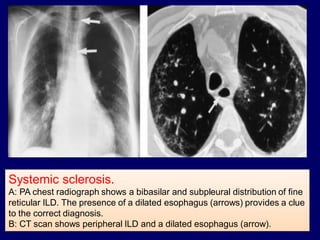

Systemic sclerosis.

A: PA chest radiograph shows a bibasilar and subpleural distribution of fine

reticular ILD. The presence of a dilated esophagus (arrows) provides a clue

to the correct diagnosis.

B: CT scan shows peripheral ILD and a dilated esophagus (arrow).

Systemic sclerosis. A: PAchest radiograph shows a bibasilar and subpleural distribution of fine reticular ILD. The presence of a dilated esophagus (arrows) provides a clue to the correct diagnosis. B: CT scan shows peripheral ILD and a dilated esophagus (arrow).